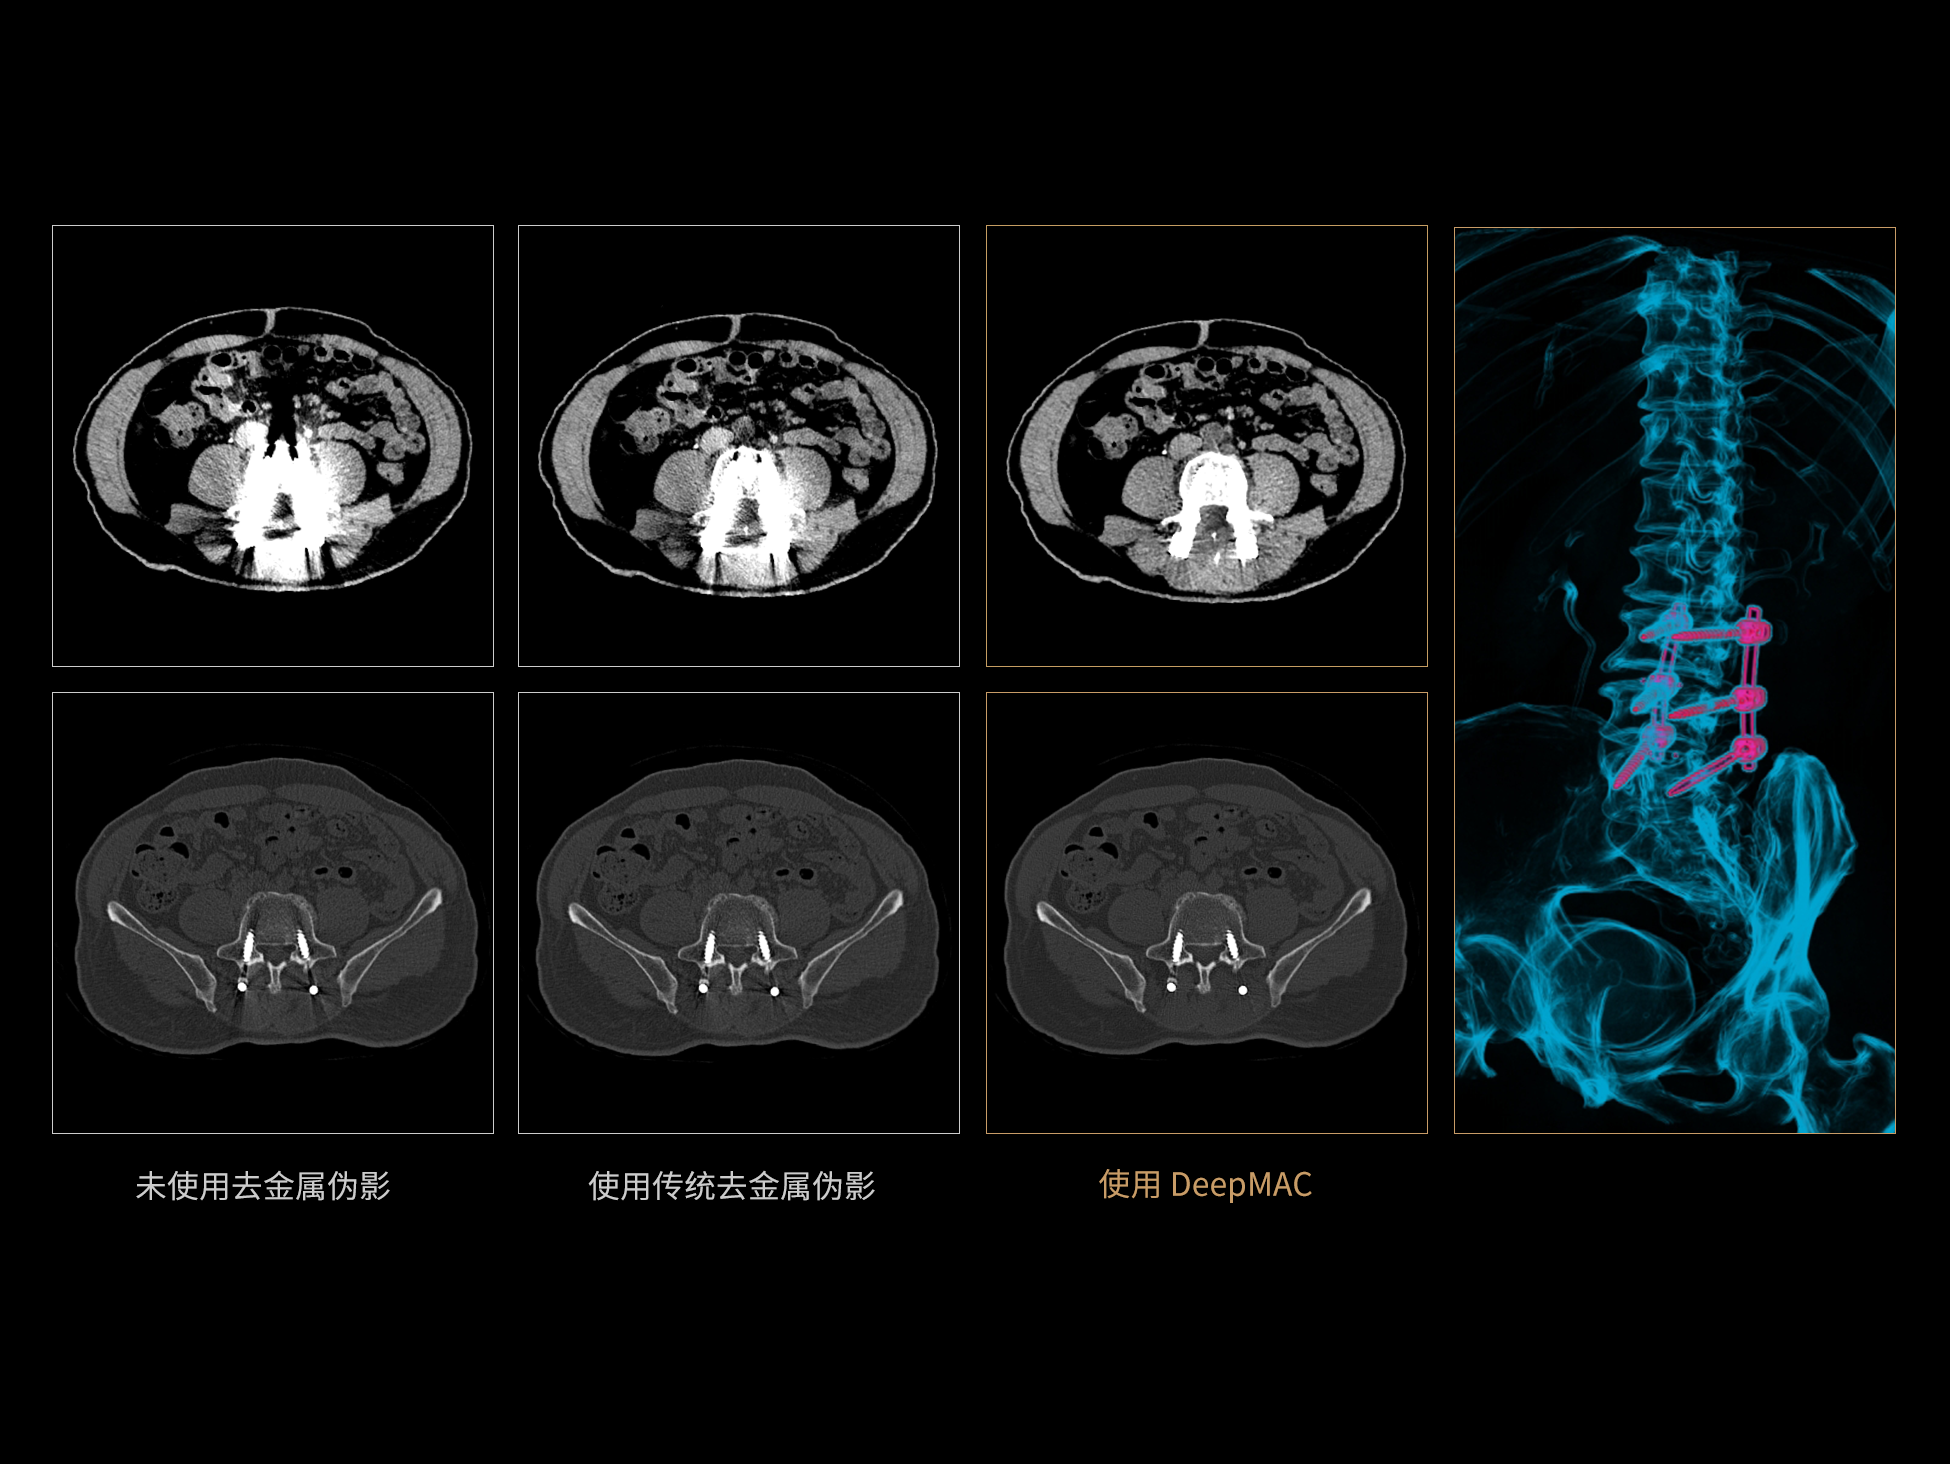

DeepMAC**:AI去金属伪影算法

DeepMAC**智能金属伪影校正技术通过深度学习算法有效解决了临床中各类不规则金属植入物导致的CT成像伪影问题,具备良好的通用性和稳定性。该技术依托大规模、高多样性的训练数据集,覆盖了包括髋关节置换体、脊柱内固定器(胸腰椎/颈椎)、四肢骨科植入物、牙科修复体以及血管介入弹簧圈等在内的金属植入物类型。通过深度神经网络的特征提取与解剖结构重建优化,DeepMAC** 在有效抑制金属伪影的同时,最大程度地保留了真实的解剖细节,显著提升了影像诊断的准确性。